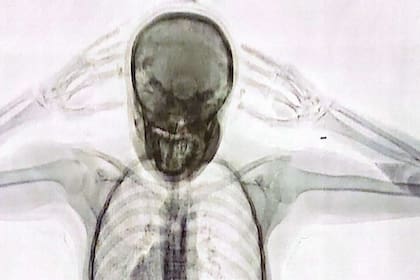

El 3 de agosto de 2023 se conoció la noticia de la detención de la “mula” narco cuando se hicieron públicas las imágenes captadas por un equipo de rayos X Body Scan que mostraban cómo se veían las 78 cápsulas con cocaína en el cuerpo de la joven pasajera.